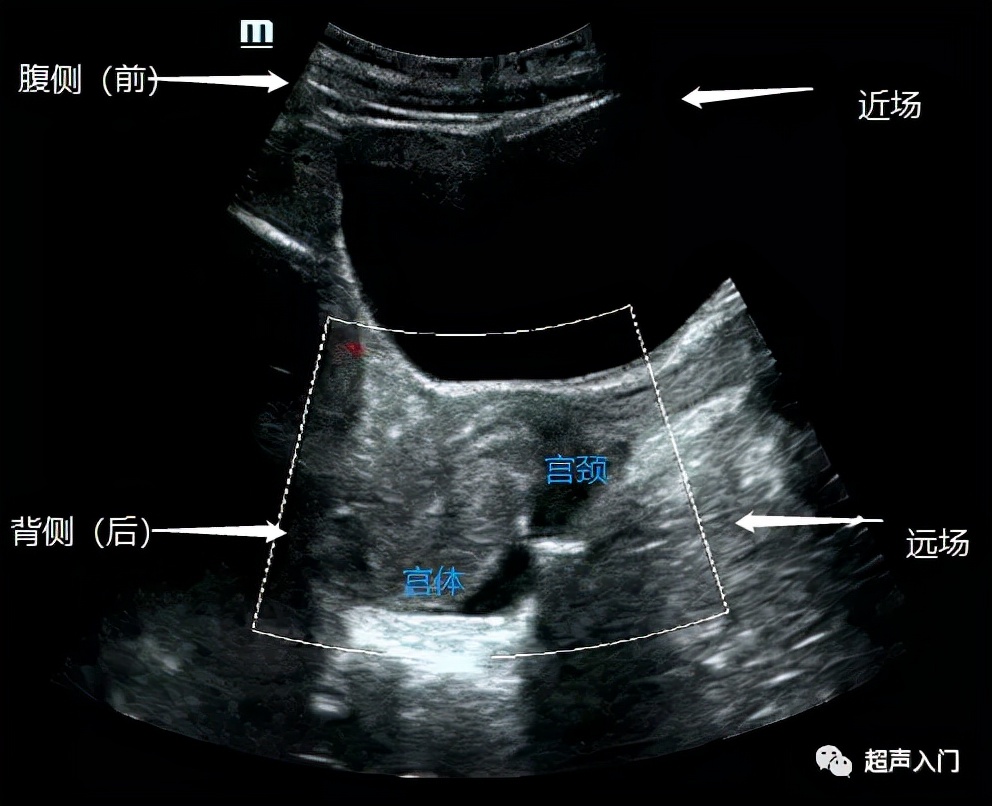

搞懂了解剖的前后,我们再来认识超声图像的前后!

前位子宫(经腹纵切面)

通过上图我们可以看出,宫体靠近腹壁侧(人体前方),因此上图为前位。